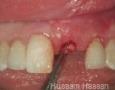

Pictures

Surgery